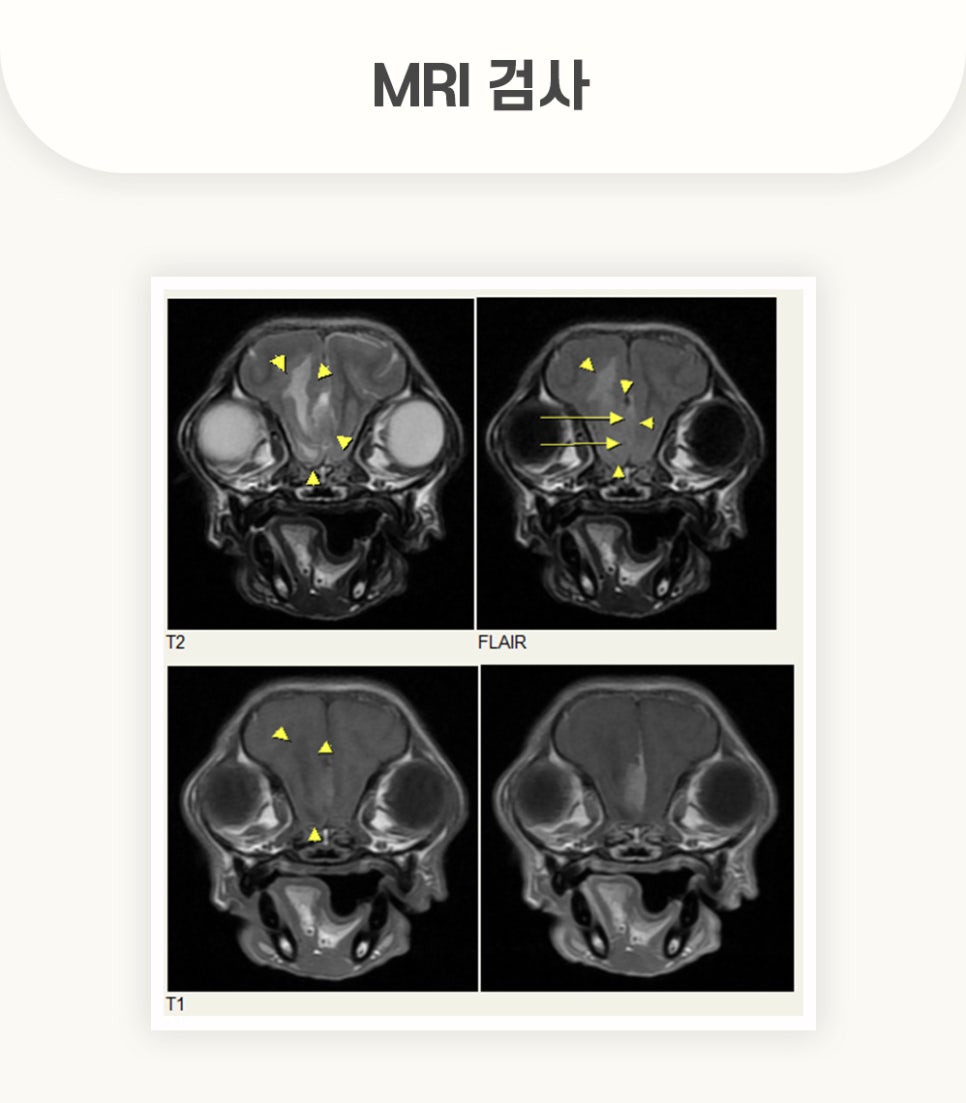

우선적으로 실행한 MRI 촬영 결과, 검사 화면에서 강아지 뇌 종양을 확인할 수 있었습니다.

전두엽 측 뇌수막종과, 원인 불명의 뇌수막염, 후두골 이형성 등이 관찰되었습니다.